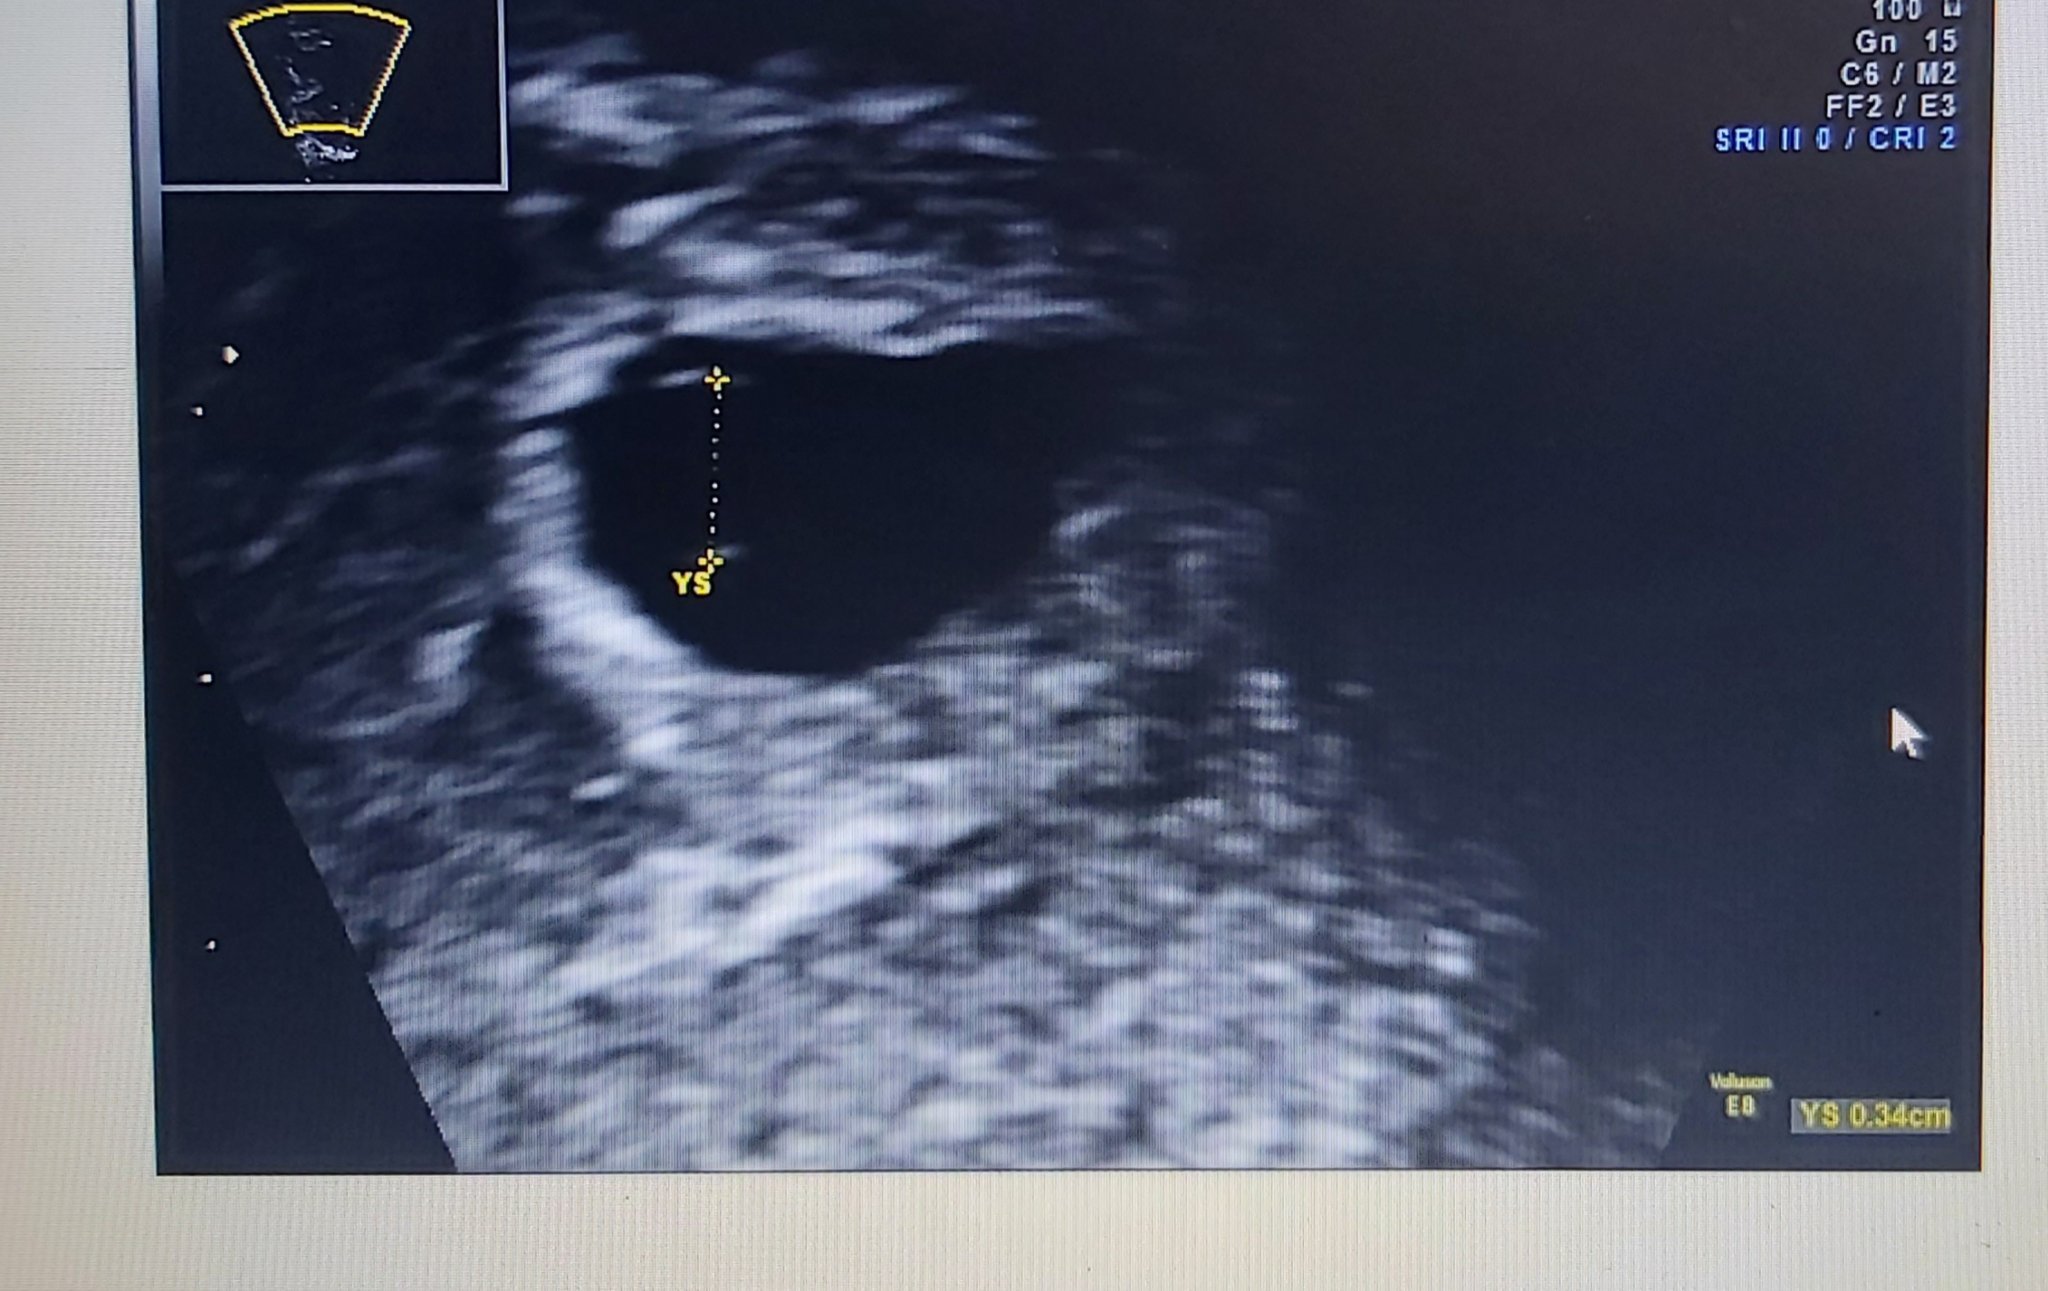

Моля, за мнение момичета! Това са снимките в 5 г.с. и 4 дни. Според вас размерите наред ли са? Сакче - 1,27см и ж.м.- 0,34 см. Предстои ми преглед да видим и чуем ембрион и сърдечна дейност и все си мисля дали се развива дали всичко е наред?🤔